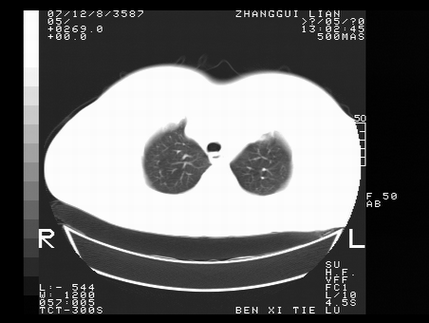

标题: CT10818:男,73,TB病史,现病史肺炎及直肠CANCER术后 [打印本页]

标题: CT10818:男,73,TB病史,现病史肺炎及直肠CANCER术后

这个请版主删除掉,这个病例我发过的,发重了,此人病史是,f,46y,胸疼,无其他原因就诊

左侧中央型肺癌伴阻塞性肺炎\\不张,左侧前上纵隔亦增宽,建议上传纵隔窗除外淋巴结转移.

考虑:左侧中央型肺癌伴阻塞性肺炎,纵隔淋巴结转移。

1)考虑为:左侧中央型肺癌伴阻塞性肺炎,纵隔淋巴结转移。2)双侧少量胸腔积液。3)心包积液。

左侧中央型肺癌伴阻塞性肺炎,纵隔淋巴结转移。

考虑左侧中央型肺癌伴阻塞性肺炎,纵隔淋巴结转移。